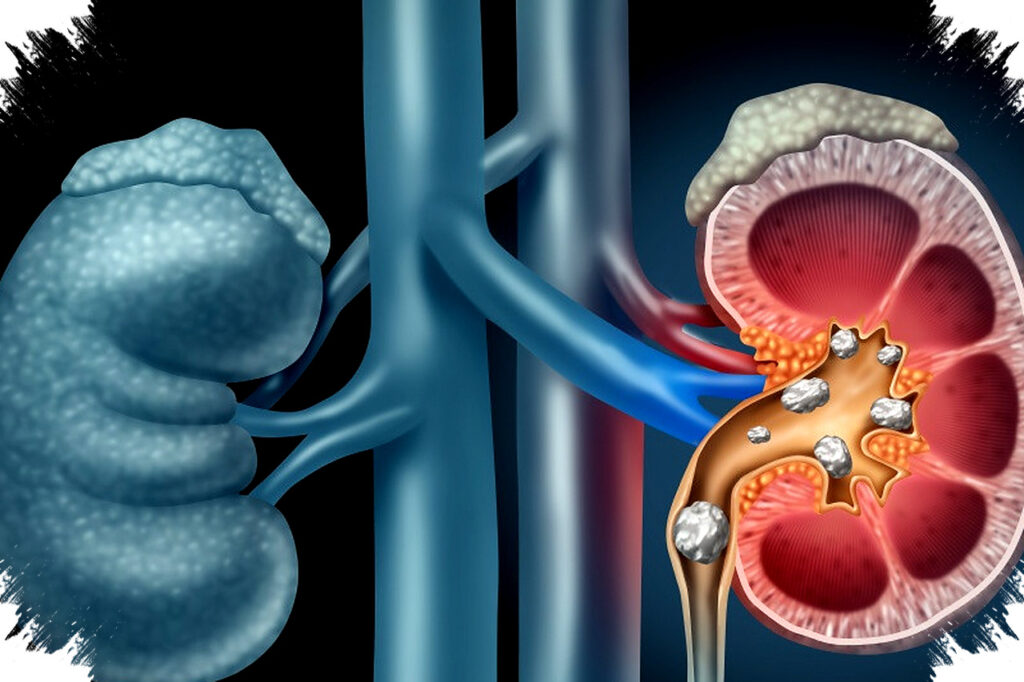

Penyakit ginjal kronik (PGK) menjadi tantangan kesehatan yang terus meningkat di Indonesia. Banyak pasien PGK mengalami anemia sebagai komplikasi yang memperburuk kondisi kesehatan mereka.

Anemia pada pasien PGK terjadi akibat berkurangnya produksi hormon eritropoietin (EPO) oleh ginjal yang rusak. EPO berfungsi merangsang sumsum tulang untuk memproduksi sel darah merah. Kekurangan hormon ini menyebabkan kadar hemoglobin menurun sehingga pasokan oksigen ke jaringan tubuh menjadi terganggu.